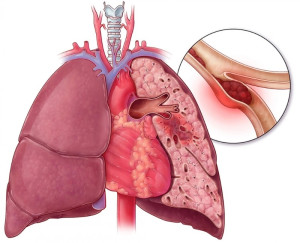

Thuyên tắc phổi (PE) là tình trạng cục máu đông hình thành trong phổi.

Nguyên nhân gây thuyên tắc phổi

Thuyên tắc phổi (PE) là tình trạng tắc nghẽn một trong các động mạch phổi, chủ yếu là do do cục máu đông di chuyển từ tĩnh mạch ở chân (huyết khối tĩnh mạch sâu - DVT) đến phổi. Thuyên tắc phổi có thể đe dọa tính mạng, nhưng nếu được chẩn đoán và điều trị kịp thời, bệnh có thể được kiểm soát hiệu quả.